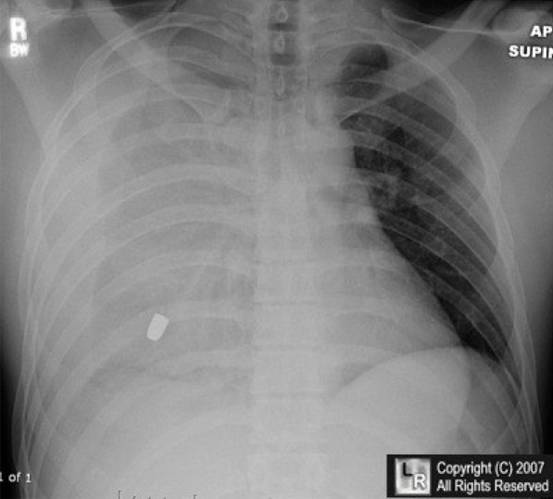

6.男性,24歲,車禍來診,訴右側(cè)胸痛,胸片如下,考慮診斷:

A. 左側(cè)氣胸

B. 右側(cè)血氣胸

C. 急性左心衰

D. 右側(cè)肺不張

E. 肺炎